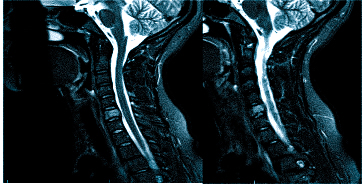

МРТ при головных болях (в трех проекциях): специальная программа выстраивает объемные изображения полученных срезов, что позволяет увидеть даже мельчайшие изменения и отдифференцировать патологию от нормы

Причин головной боли множество, и их не всегда возможно определить без помощи современных способов визуализации. Цефалгию вызывают: повышенное внутричерепное давление, сосудистые мальформации, опухолевые процессы, постравматические осложнения. Какую МРТ делать при головной боли или предпочтительней пройти КТ — зависит от предполагаемого характера патологии. Все методы являются взаимодополняющими, но что лучше в конкретном случае, выбирает врач с учетом жалоб, показаний и противопоказаний. МРТ и КТ с контрастным усилением позволяют получить сопоставимые по качеству снимки, но при этом используют разные принципы построения изображений. Чем раньше будет найдена причина и проведено адекватное лечение, тем больше шансов на полное выздоровление.